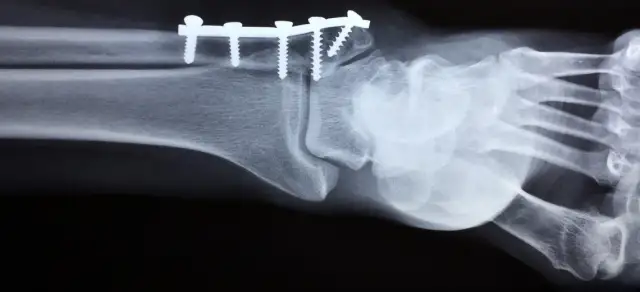

Operacja haluksa: NFZ czy prywatnie? Porównaj metody, koszty (od 7 000 zł), czas oczekiwania i wybierz najlepszą klinikę. Sprawdź nasz przewodnik!